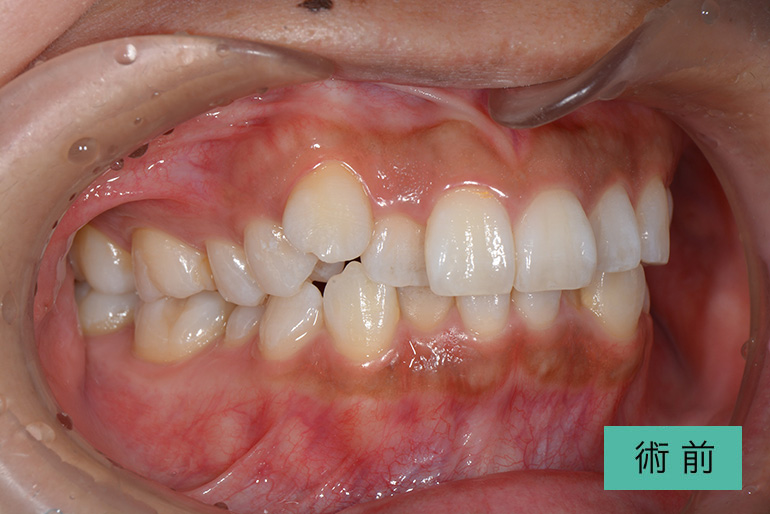

オールセラミック①

| 治療内容 | 上顎インビザライン矯正 右上1番から左上の2番のセラミック冠 上顎前歯の叢生、右上犬歯の捻転の改善のため、上顎のみインビザライン矯正を行なった また、根尖病巣があった為補綴を除去、顕微鏡根管治療を行い、セラミック冠を装着した |

| 治療期間・回数 | 約8ヶ月、15回(インビザライン矯正) 約4ヶ月、6回(補綴治療) |

| 費用(税込) | ¥275,000 (上顎インビザライン矯正) ¥495,000(165,000/1本)(補綴費用) ※自由診療 |

| リスク・副作用 | 疼痛、補綴物の脱落、咬合違和感、破折 |